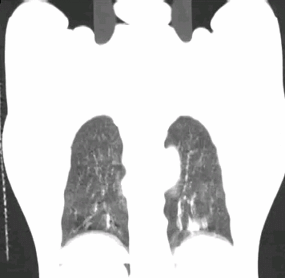

现场展示D4D呼吸门控扫描病例,可清楚观察肿瘤本身随呼吸周期运动情况。

Discovery CT590 RT的Deviceless 4D扫描技术可以进行无附件四维CT扫描,动态追踪内部解剖结构运动,多参数呼吸特征提取,呼吸期相实时匹配,肿瘤运动范围的显示更准确,为精准放射治疗提供更多信息。